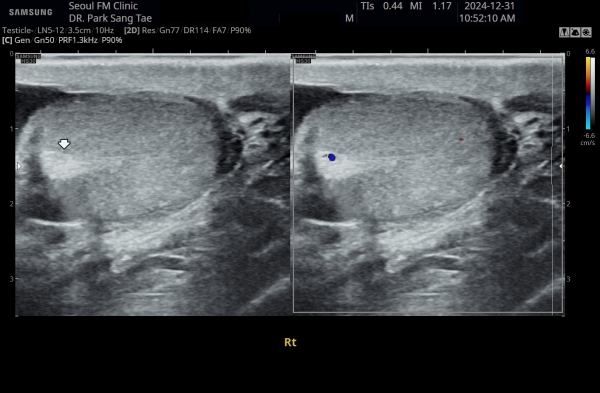

약 8개월 전 전립선과 전립선관,사정관,사정관입구,정낭 그리고 정관의 표적 치료전 우측 정관과 고환의 순환장애로

고환의 섬유화가 관찰되는 초음파 사진입니다.

This ultrasound image, taken about 8 months ago before starting targeted treatment of the prostate, prostatic ducts, ejaculatory ducts, seminal vesicles, and vas deferens, shows poor circulation in the right testicle. Due to this circulation problem, some fibrosis (scarring) of the testicle can be observed.

약 8개월후 전립선과 전립선관,사정관,사정관입구,정낭 그리고 정관의 표적 치료후 우측 정관과 고환의 순환장애가 치료되어

고환의 섬유화가 치료된 초음파 사진입니다.

This ultrasound image, taken about 8 months after starting targeted treatment of the prostate, prostatic ducts, ejaculatory ducts, seminal vesicles, and vas deferens, shows improved circulation in the right testicle. The previous scarring (fibrosis) has healed, indicating that the circulation problem in the vas deferens and testicle has been successfully treated.